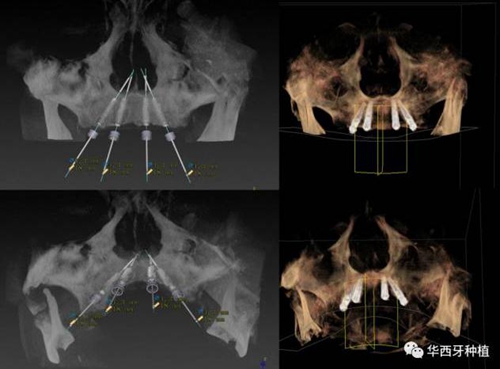

吳教授提到了使用數(shù)字化建模與導板的聯(lián)合應用,不僅可以從設計上降低修復難度,便于在修復為導向的設計中種植體方向的確定,同時可以加入微創(chuàng)的手術方法,減輕術中創(chuàng)傷。

對于傳統(tǒng)的all-on-four術式,吳教授加入了微創(chuàng)的指導思想,設計時同樣加入數(shù)字化三維重建與修復一體化設計,增加了手術的可控性,同時極大減輕了患者的創(chuàng)傷程度,縮短了修復周期。

演講結束前,吳教授再次提到了數(shù)字化對口腔全口牙缺失種植修復一體化的重要性,構建一體化的數(shù)字化種植修復流程,不僅能輔助手術,更是簡化修復和確保遠期療效的一把利器。